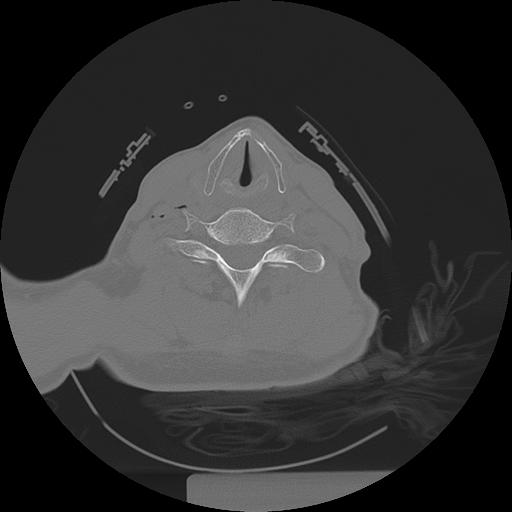

11 HUESO,,Axial,2.0,HUESO,,